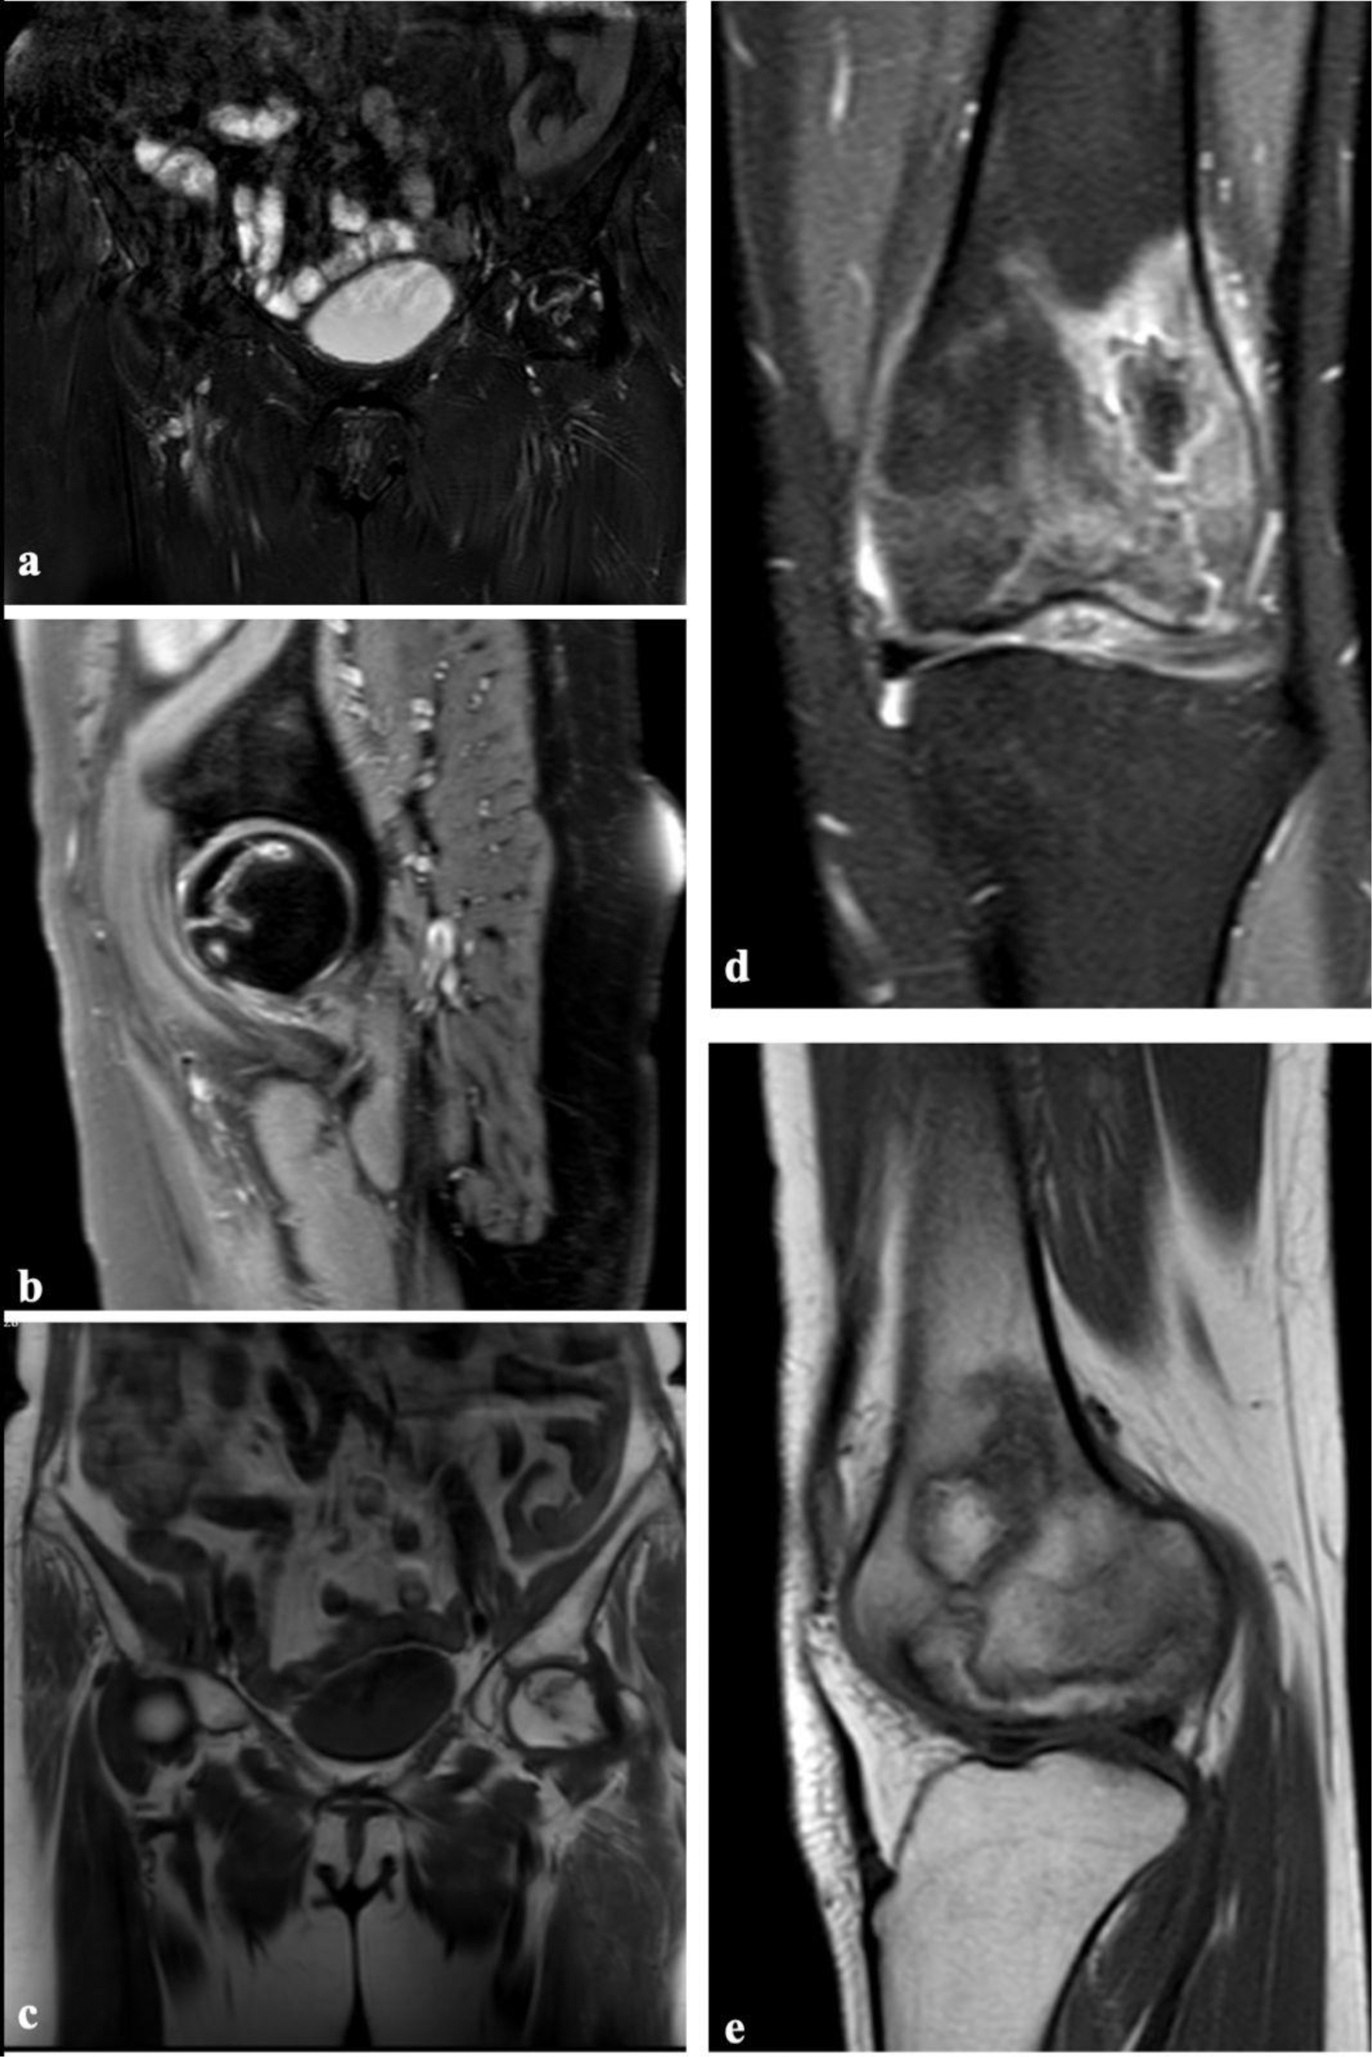

Methods: This single-center, retrospective study included patients diagnosed with various rheumatic diseases who developed AVN following corticosteroid therapy. AVN was confirmed via imaging performed due to pain symptoms during routine outpatient visits (Figure 1). A control group was established, consisting of patients with the same diagnoses who had not developed AVN. Controls were matched in a 1:1 ratio based on age, gender, rheumatologic diagnosis, and cumulative corticosteroid dose. Data collected from patient records included demographic characteristics, underlying diagnoses, corticosteroid doses and durations, time to AVN diagnosis, imaging findings, and AVN-related treatments. The cumulative CS dose was calculated, and the time between corticosteroid initiation and AVN development was analyzed. Differences in AVN onset and frequency among rheumatologic diseases were also evaluated. CS dosing was categorized as follows: low dose: ≤7.5 mg/day of prednisolone (PRD), moderate dose: 7.5–30 mg/day of PRD, high dose: 30–100 mg/day of PRD, and pulse dose: >100 mg/day of PRD.

Examples of Avascular Necrosis on Magnetic Resonance Imaging Figure 1a, b, and c demonstrate an example of hip avascular necrosis (AVN) in coronal fat-suppressed T2-weighted sequence (a), sagittal fat-suppressed T2-weighted sequence (b), and coronal T1-weighted sequence (c), showing geographic signal changes in the femoral head while preserving the femoral contour and acetabulum. Figure 1d and e present an example of AVN in the left femur, shown in coronal fat-suppressed T2-weighted sequence (d) and sagittal T1-weighted sequence (e), displaying geographic signal changes and significant edema in the distal metaphyseal-diaphyseal region of the left femur.